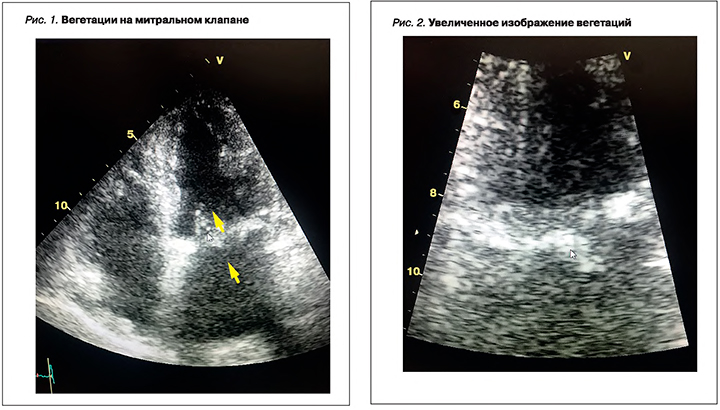

На 10-й день пребывания в стационаре (22.11.2019) при ЭхоКГ, проведенном в рамках диагностического поиска генеза лихорадки, впервые были выявлены два дополнительных образования на деформированном митральном фиброзном кольце и подклапанных структурах митрального клапана (рис. 1, 2). Одно из них было подвижным и пролабировало в полость левого предсердия, округло-продолговатой формы, размерами 1,4×0,8 см. Также определялся выпот над правым предсердием с сепарацией листков перикарда до 0,5 см как проявление полисерозита в рамках системной воспалительной реакции.

В стационаре проводился мониторинг ЭхоКГ каждые 7 дней и на 32-й день терапии. При контрольной ЭхоКГ исчезли вегетации на митральном клапане (рис. 3, 4), уменьшился объем правого предсердия и несколько снизилось систолическое давление в легочной артерии, исчез выпот в полости перикарда.